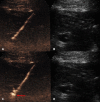

The introduction of ultrasound contrast agents has rendered contrast-enhanced ultrasound (CEUS) a valuable complementary technique to address clinically significant problems. This pictorial review describes the use of CEUS guidance in abdominal intervention and illustrates such application for a range of clinical indications. Clinical application of CEUS discussed include commonly performed abdominal interventional procedures, such as biopsy, drainage, nephrostomy, biliary intervention, abdominal tumor ablation and its subsequent monitoring, and imaging of vascular complications following abdominal intervention. The purpose of this article is to further familiarize readers with the application of CEUS, particularly its specific strength over alternative imaging modalities, in abdominal intervention.